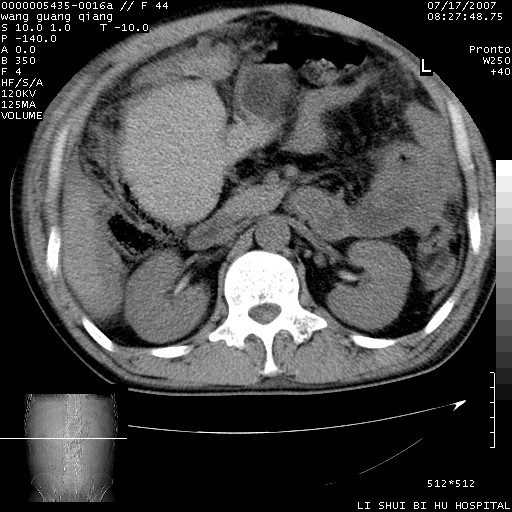

以下是引用dyqct在2007-7-18 10:46:00的发言:[br]胆囊明显增大,壁增厚,明显强化;后下方见大片高密度区,ct值68hu,无强化,周围见多数条纹状高密度影,边界不清。双膈下间隙、肝肾隐窝见带状及片状低密度区。[br]右侧胸壁后缘亦见新月形水样密度区。[br]考虑:1、急性胆囊炎伴周围出血;[br] 2、少量腹水、右侧少量胸腔积液。[br][br][本贴已被 dyqct 于 2007-7-18 10:48:47 修改过]